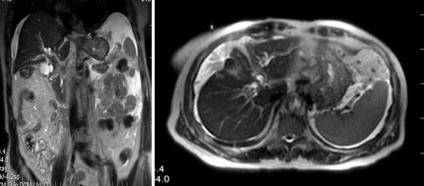

Több máj- hydatid cisztákat és ciszta egység a lépben

Eredményeként keletkezik fertőzéses folyamatok fejlesztése máj sérülések utáni műveletek, portál véna visszérgyulladás, szepszis.

Megnyilvánuló súlyos hipertermia, tachycardia, a diszpepsziás tünetek, valamint a fájdalom és puffadás tipikus lokalizáció.